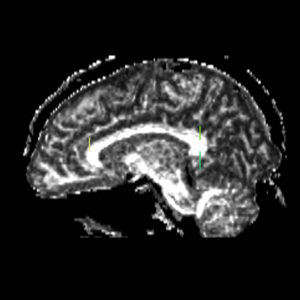

Boundaries for the ROI's, mainly using FA maps & color by orientation, followed by the color coding of the labelmaps.

Cingulum BundleROI 1) on the superior side of the corpus, flush with the most anterior part of the corpus (based on sag view, but drawn on coronal view) ROI 2) on the first coronal slice where the L & R corpus connect, on the superior side of the corpus. ROI 3) on the first coronal slice where the L & R corpus connect, on the inferior side of the corpus. ROI 4) on the first coronal slice where the middle cerebellar peduncle is present.